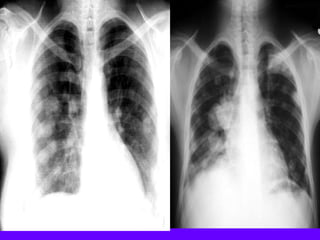

Necrotizing Pneumonia / Lung Abscess / Aspiration

Superior segment RLL dense pneumonia

Progression / Cavity